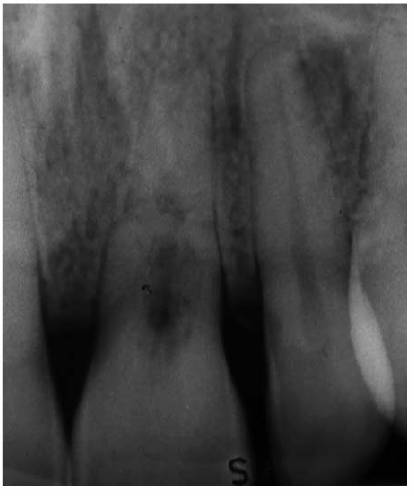

Transillumination via a fiber-optic light may be of great assistance in

detecting color shifts in a crown (Figures 19-1A, and 19-1B). A tooth with a pink or reddish

hue would more than likely indicate internal hemorrhage from a recent injury (Figure 19-2), a dental procedure (Figure 19-3), or gingival tissue hyperplasia

Figure 19-1A: Transillumination of a maxillary left central incisor with a necrotic pulp.

Figure 19-1B: Transillumination of the adjacent tooth with a vital pulp. Because there is active blood flow through the live pulp tissue, the tooth appears brighter to the fiber-optic light than the adjacent tooth with a necrotic pulp.

Figure 19-4A: Pink spot as a result of external resorption.

Figure 19-4B: Radiograph of the same tooth showing external resorption.

Figure 19-4C: Pink spot as a result of internal resorption.

Figure 19-4D: Radiograph of the same tooth showing internal resorption.